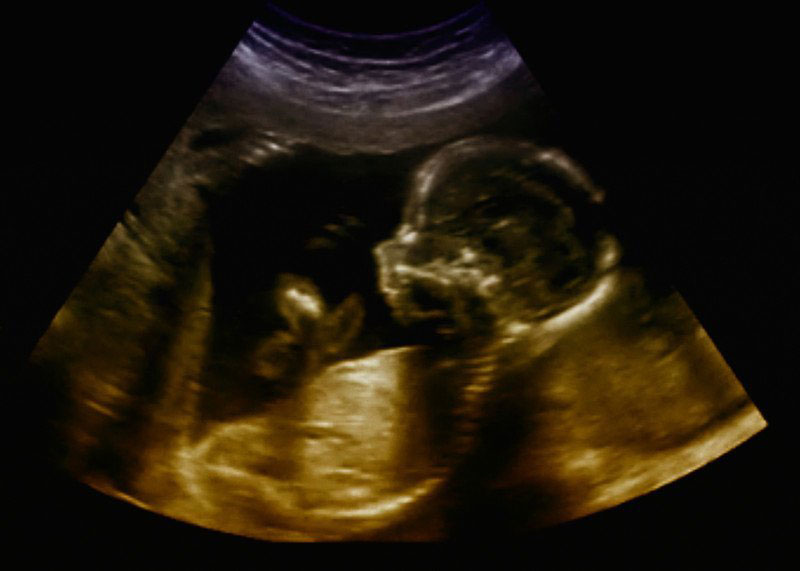

Siêu âm là một bước quan trọng trong vấn đề chăm sóc sức khỏe hiện đại, đặc biệt là trong thai kỳ, qua đó giúp cung cấp những hình ảnh có giá trị về sức khỏe của cả mẹ và thai nhi.

Với những tiến bộ của khoa học và công nghệ, các phương pháp siêu âm hiện nay đã phát triển đáng kể, bao gồm nhiều loại hình như quét 2D, 3D và 4D. Mỗi loại đều có những ưu điểm riêng biệt, chất lượng hình ảnh khác nhau và chi phí liên quan. Việc lựa chọn hình thức siêu âm nào sẽ phụ thuộc vào một số yếu tố và bác sĩ sẽ có chỉ định phù hợp nhất dựa trên tình trạng cụ thể của từng người.

Loại hình siêu âm ba chiều này mang lại hình ảnh chi tiết và chân thực hơn về thai nhi trong bụng mẹ.

Siêu âm 4D

Dựa trên công nghệ 3D, siêu âm 4D cho phép ghi lại chuyển động của thai nhi rõ ràng, chi tiết. Siêu âm 4D giúp cha mẹ có thể tận mắt chứng kiến những cử chỉ và biểu cảm đầu tiên của con mình. Đổi lại, chi phí siêu âm 4D sẽ tương đối cao.